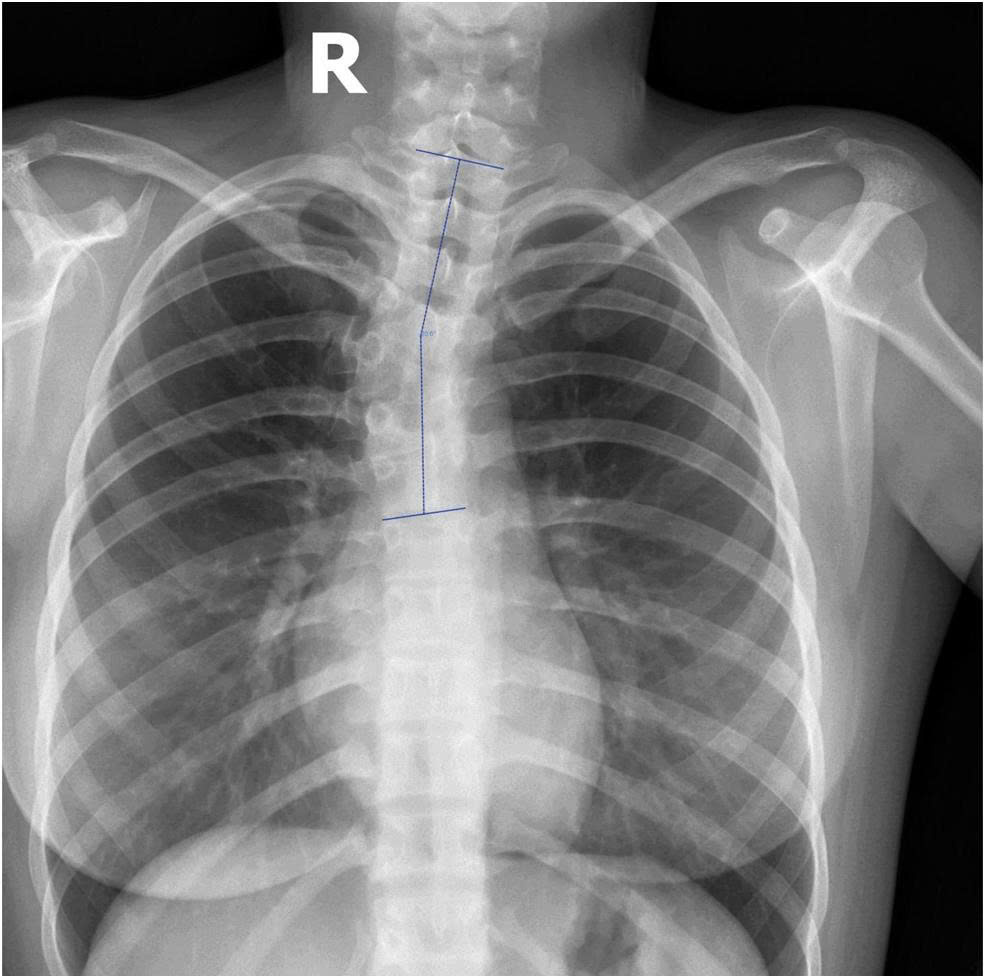

Hình 2: Bất thường mạch máu trong ống sống đi kèm.

Nếu con bạn, đặc biệt là ở lứa tuổi dậy thì, có dấu hiệu đau lưng không rõ nguyên nhân, vai lệch, hoặc một bên hông cao hơn bên kia, đừng bỏ qua. Hãy đưa trẻ đi khám bác sĩ chuyên khoa cột sống. Các phương pháp chẩn đoán hình ảnh như chụp X-quang, CT scan (chụp cắt lớp) hoặc MRI (chụp cộng hưởng từ) sẽ giúp bác sĩ xác định chính xác tình trạng đốt sống bán phần và mức độ cong vẹo.

Điều quan trọng cần biết là, dị tật đốt sống bán phần thường không xuất hiện đơn độc. Nó có thể là tín hiệu cảnh báo cho nhiều bất thường tiềm ẩn khác trong cơ thể, đặc biệt là ở tim, thận hoặc các hệ cơ quan quan trọng khác. Chính vì vậy, câu chuyện của em không chỉ là hành trình tìm kiếm sự chữa lành cho cột sống, mà còn là lời nhắc nhở khẩn thiết về tầm quan trọng tối đa của việc đi khám bệnh sớm và toàn diện khi phát hiện bất kỳ dấu hiệu bất thường nào. Đừng bỏ qua những triệu chứng nhỏ, vì chúng có thể là manh mối dẫn đến một chẩn đoán quan trọng, mở ra cánh cửa cho việc can thiệp kịp thời và bảo vệ sức khỏe tổng thể của trẻ.